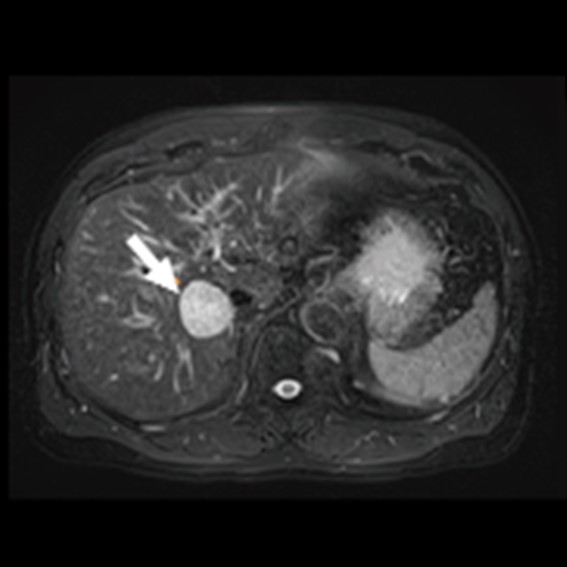

運用高科技尖端影像設備,提供貴賓精準的檢查、判讀、即時醫療、後續追蹤、健康管理或醫學中心轉介服務;從健檢診斷到後端治療,一條龍式服務。永越自成立以來,已服務超過16萬人次,每年通報件數超過千件,揪出包括:甲狀腺癌、肝腫瘤、肺癌、乳癌、子宮頸癌等重大異常的健康警訊,把握住早發現早治療的黃金關鍵。